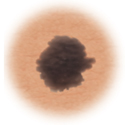

Lunares (nevos)

Son marcas pequeñas en la piel que se deben a las células que producen el pigmento. Los lunares pueden ser planos o elevados, lisos o ásperos y algunos tienen pelos. La mayoría es de color marrón oscuro o negro, pero algunos son amarillentos o del color de la piel. Los lunares pueden cambiar con el tiempo y a menudo reaccionan a los cambios hormonales.

En la mayoría de los casos, los lunares son benignos y no se necesita tratamiento. Algunos lunares benignos pueden convertirse en cáncer de piel (melanoma). A continuación puede consultar los signos de que un lunar se está volviendo canceroso.

Lunar normal.